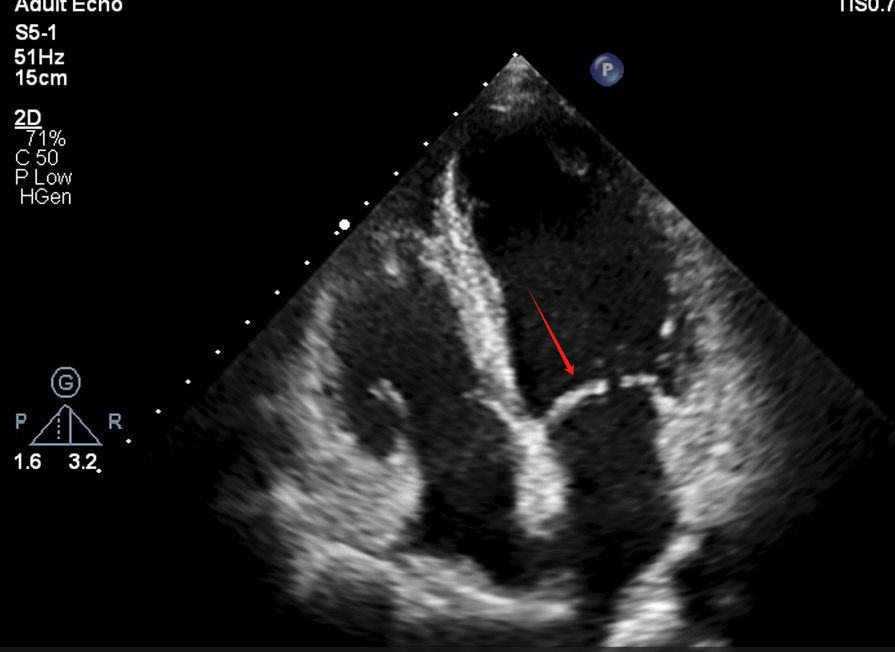

箭头所指结构为:( )

选项:

A:三尖瓣

B:主动脉瓣

C:二尖瓣

D:肺动脉瓣

答案: 【二尖瓣】